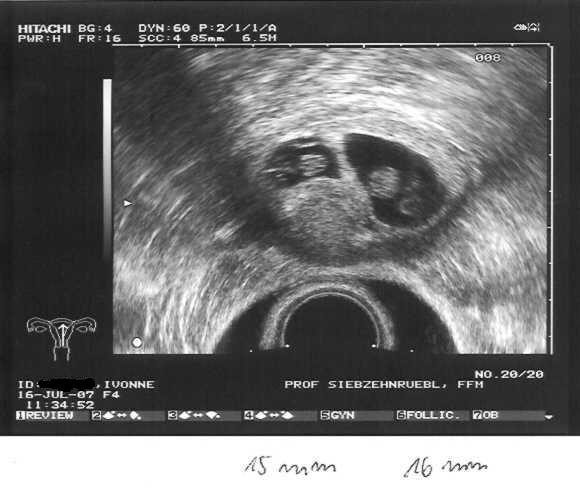

Ab heute ist es Amtlich wir bekommen Zwillinge :baby: :baby: beide Herzlein schlagen. Wir können unser Glück garnicht fassen. *rotfl* *pfeif*

Den US hat heute Fr. Dr. Weidner gemacht, da in der Praxis wohl jemand Kollabiert ist und sie Daher unter Zeitdruck gestanden haben. Beide Babys waren gut zu sehen das eine ist 15mm und das andere 16mm groß. Allerdings hat Fr.Dr Weidner gesagt das ich von der Entwicklung her erst in der 7+6 wäre.

US 16.07.07 2 Herzlein schlagen Zwillinge

Schon schön anzusehen dein US Bild, SCCCHHHÖÖNNNN.